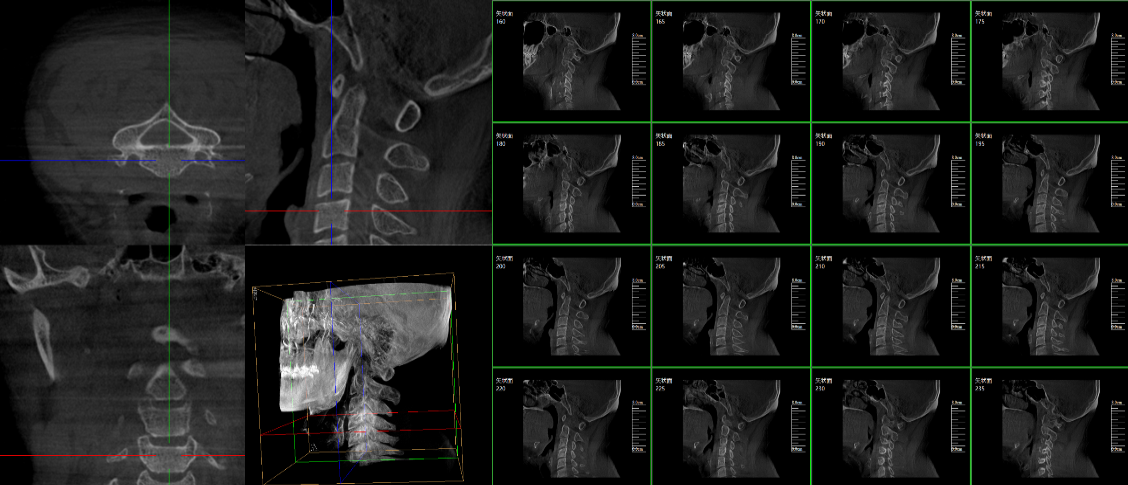

PLX7500三維c型臂臨床應用:

脊柱外科的應用:有研究表明,在三維c型臂圖像引導的下頸椎或胸椎后路螺釘置入術中,螺釘正確置入率可達92.7%,在三維c型臂圖像引導的椎間孔腰椎椎間盤融合術中,術者被輻射總量明顯降低。此外三維c型臂可以搭配骨科手術導航和機器人使用,能將該過程智能化和準確化,進一步提高螺釘的植入率。

截骨矯形外科中的應用:胸腰段是脊柱應力相對集中區域,因此,該節段更易發生骨折,且骨折術后更易并發角狀后凸畸形,大多數患者都需二次手術矯正。他們認為術中三維c型臂輔助后路螺釘置入并半椎體切除矯形治療兒童先天性脊柱后突畸形患者時,螺釘置入精度高且安全,截骨矯正效果滿意。

創傷外科的應用:由于創傷外科的患者多數為急、重癥患者,以致術前準備時間較短,很多都需行急診手術,三維c型臂可以在術中實時重建三維圖像,使手術醫生對一些復雜骨折更加充分的了解,并且能夠在術中即時校正螺釘的位置,更加精確地置入固定器材,減少術中及術后發生并發癥的幾率,極大限度地縮短螺釘置入時間。